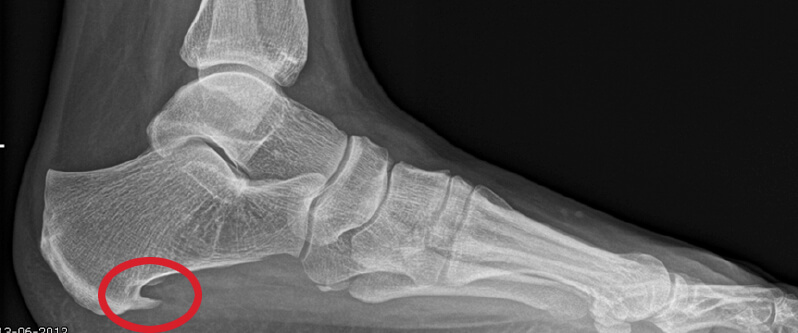

Hielspoor duidelijk zichtbaar op deze op röntgenfoto.

Een hielspoor is een botuitwas (verkalking) aan de onderzijde van het hielbot, het zogenoemde calcaneus. Deze verkalking bevindt zich op de plaats waar de peesplaat onder de voet, de fascia plantaris, aanhecht. Een hielspoor is goed zichtbaar op röntgenfoto’s en kan ook met echografisch onderzoek worden vastgesteld.